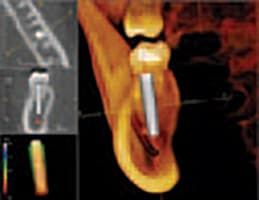

IN THE PAST, DENTAL DAYDREAMERS PONDERED THE ABILITY TO CAPTURE A 3-D IMAGE OF THE MOUTH AND TO VIEW IT FROM ALL ANGLES. The ability to rotate that 3-D mode and zoom in on details was an even greater aspiration. Then, to coordinate all of the information for integration with other applications- such as guided implant placement software-promised to add even more value to the technology. All of these benefits are not just relegated to the dental visionaries of the future. 3-D imaging is available, here and now, and is actively improving practices across all dental disciplines. IMPLANTOLOGY Jack T. Krauser, DMD: 3-D radiography has made an astonishing and

Cone Beam CT: A Breakthrough Imaging Technology for Dentistry

ABSTRACT: Accurate images of the craniofacial region are critical for the development of a diagnosis and treatment plan. The Cone Beam CT (CBCT) Scanner represents a significant advance in imaging capabilities for all disciplines of dentistry. This new-generation scanner uses computed tomography technology to provide a complete three-dimensional view of the maxilla, mandible, teeth, and supporting structures with relatively high resolution and low radiation exposure to the patient. This article discusses some of the technical aspects of CBCT and its possible dental usages. INTRODUCTION: Images of the craniofacial region comprise an important component of the dental patient record. Ideally, the imaging process begins with the development of an imaging goal. The imaging

2-D imaging (standard film and digital X-rays) has long been the standard for dental scans-despite the somewhat costly price and high radiation dosages. Now 3-D imaging technology is set to address these issues. Cone Beam technology obtains crucial information at much higher resolution using lower radiation, and is cost-effective for practitioners and patients. Indeed, such important benefits will certainly give traditional 2-D X-ray imaging a run for its money. THE INTRODUCTION OF CONE BEAM TECHNOLOGY Here's where 3-D imaging is invaluable. It lets dentists see patients' anatomies in all dimensions by creating a 360° analysis. These images give dental professionals a complete makeup of the human jaw, face, and